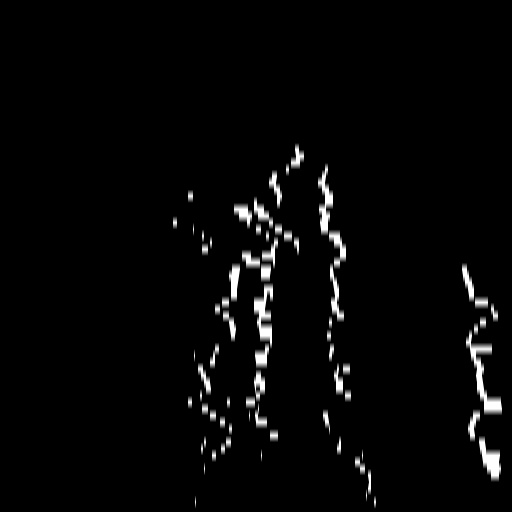

A.2 Temporal Coherency

Our method takes an entire X-ray video as input, thus producing segmentation results with better temporal coherency. Temporal coherency is essential for making medical diagnoses, especially when dealing with blood flow in vessels. Therefore, we conduct visual comparisons between our method and other compared methods by slicing horizontally or vertically and stacking the segmentation results. The results in Figure 11 show our method strikes a better balance between segmentation accuracy and temporal coherency. While other baseline methods either produce false segmentation results or do not maintain consistent prediction along the temporal dimension.